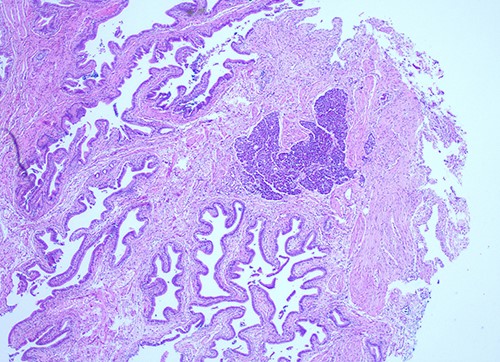

She proceeded to an elective laparoscopic cholecystectomy. At the time of her procedure, she was found to have features suggestive of chronic cholecystitis with peritoneal adhesions. Her procedure was straightforward and intraoperative cholangiogram showed a spiral cystic duct with the trifurcation of intrahepatic ducts. Her common bile duct appeared mildly dilated however tapered at the lower end and showed filling of the duodenum with no filling defects. The histology from the gallbladder showed variable fibromuscular thickening of the wall with intramural cystic Rokitansky-Aschoff sinuses, but no significant inflammation. Focal ectopic pancreatic acinar tissue (1 mm) within the gallbladder was found (Figs 1–3). There was no evidence of intestinal metaplasia, dysplasia or malignancy.

Histological examination of gallbladder ×40 showing island of ectopic pancreatic tissue adjacent to the mucosa of the gallbladder neck.